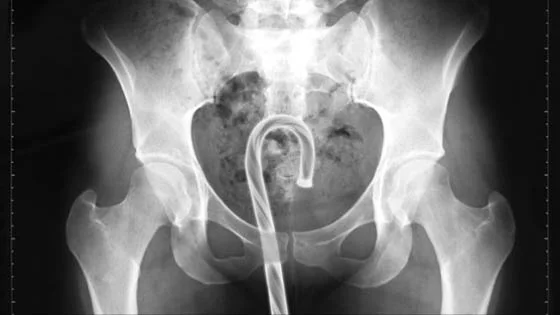

• CROCHET NEEDLE